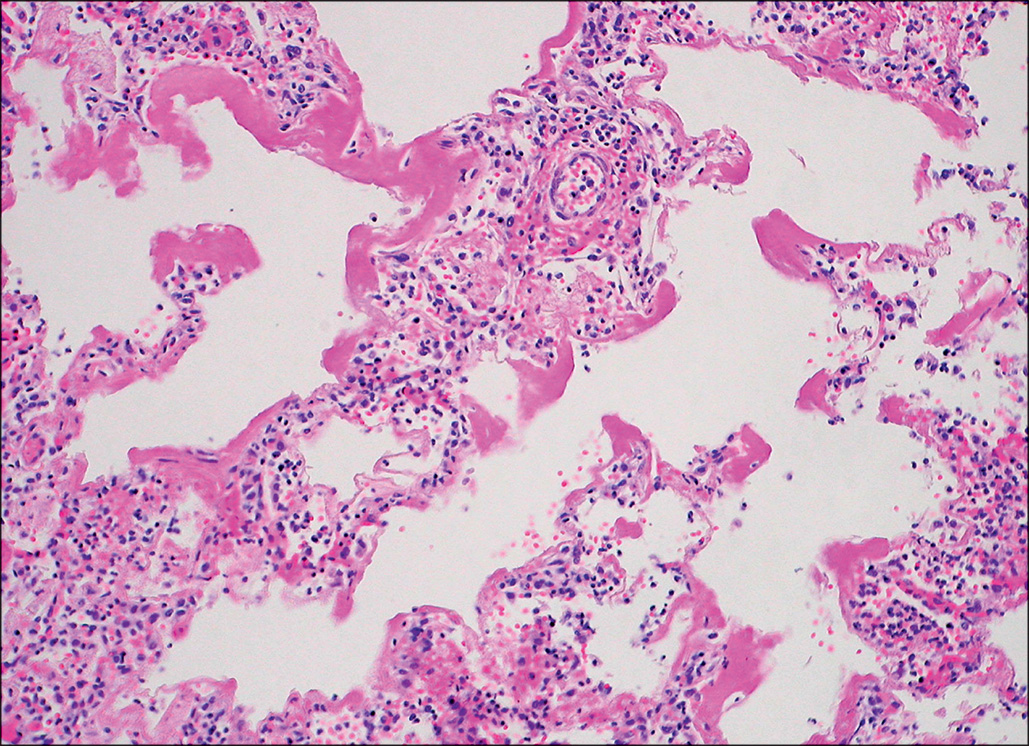

In patients who have clinical evidence of sepsis at the time of death, extensive infection of the lungs is commonly present. Fatal pneumonia is most often seen as a consequence of infection with a highly antibiotic-resistant bacterial strain. Virulent and antibiotic-resistant strains of Pseudomonas or Acinetobacter may produce an angioinvasive infection in the lung, with massive proliferation of bacteria within the walls of pulmonary artery branches and necrosis of nodules of lung tissue in all lobes ( Figs. 38.3–38.5 ). This pattern is similar to that of ecthyma gangrenosum of the skin, which is also characterized by bland necrosis thought to be a result of ischemia. , A similar angioinvasive pattern of pulmonary infection can be seen with generalized infection caused by Aspergillus or similar filamentous fungi.

This micrograph, taken at low magnification, shows a small round pale area of necrotic lung tissue in which no nuclei are staining, surrounded by a zone of congestion and hemorrhage, with very little acute inflammatory reaction. H&E stain.